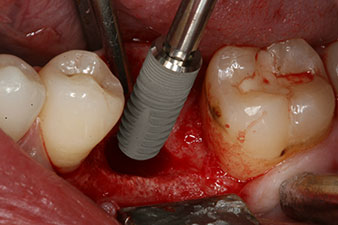

El torque en el momento de la carga mecánica fue de 43 Ncm. Asimismo, después de atornillar un poste de medición especial adaptado al sistema de implante (SmartPeg), el valor ISQ se determinó con la sonda del módulo Osstell ISQ de W&H.

Este módulo Osstell ISQ que se encuentra disponible como accesorio para la unidad Implantmed de W&H y se acopla al motor de implantes (véase figura 11). El valor ISQ adimensional fue de 64 justo en el momento de la inserción en la dirección bucovestibular y de 68 en la dirección mesiodistal (valor máximo = 100).